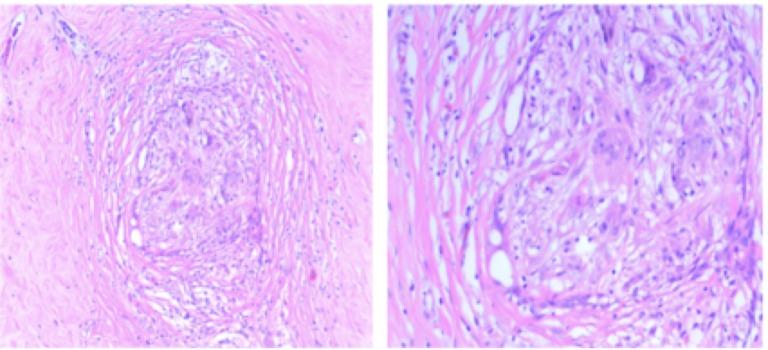

We report on a 56-year-old Caucasian female, diagnosed with locally advanced, hormone-receptor-positive, and human epidermal growth factor receptor 2 (HER2)-positive cancer of the left breast. The patient received neoadjuvant chemotherapy with adriamycin/cyclophosphamide (AC) followed by docetaxel/trastuzumab. A partial clinical and radiographical response was documented after four cycles of AC. Approximately one week after the first cycle of docetaxel and trastuzumab, the patient presented with diffuse edema, erythema, and induration involving the entire left breast. The differential diagnoses included infection, inflammatory response/reaction to docetaxel, or cancer progression. After a multidisciplinary review, the decision was made to stop the docetaxel and deliver neoadjuvant radiation treatment concurrent with trastuzumab. Approximately four weeks after radiation therapy completion, the patient underwent a left total mastectomy and axillary dissection, with pathologic complete response (pCR) in the breast and axillary nodal disease. After surgery, systemic therapy was resumed with paclitaxel and trastuzumab, with a plan to start adjuvant endocrine therapy after completion of chemotherapy. We will discuss clinical considerations in the management of the unexpected findings of acute inflammatory response in the breast and nodal regions during neoadjuvant chemotherapy. Associations between intrinsic breast cancer subtype and pCR in locally advanced breast cancer will also be reviewed.

我们报告了一名56岁的白种女性,被诊断为左乳局部晚期、激素受体阳性且人表皮生长因子受体2(HER2)阳性的癌症。患者接受了阿霉素/环磷酰胺(AC)新辅助化疗,随后接受多西他赛/曲妥珠单抗治疗。在4个周期的AC化疗后记录到部分临床和影像学缓解。在多西他赛和曲妥珠单抗的第一个周期后约一周,患者出现累及整个左乳的弥漫性水肿、红斑和硬结。鉴别诊断包括感染、对多西他赛的炎症反应或癌症进展。经过多学科会诊后,决定停止多西他赛治疗,并在曲妥珠单抗治疗的同时进行新辅助放疗。放疗完成约四周后,患者接受了左乳全切术和腋窝淋巴结清扫术,乳腺和腋窝淋巴结疾病达到病理完全缓解(pCR)。术后,恢复了紫杉醇和曲妥珠单抗的全身治疗,并计划在化疗完成后开始辅助内分泌治疗。我们将讨论新辅助化疗期间乳腺和淋巴结区域急性炎症反应意外发现的临床处理要点。还将回顾局部晚期乳腺癌的内在亚型与pCR之间的关联。